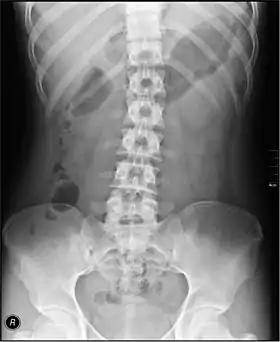

The standard abdominal X-ray protocol is usually a single anteroposterior projection in supine position.[15] A Kidneys, Ureters, and Bladder projection (KUB) is an anteroposterior abdominal projection that covers the levels of the urinary system, but does not necessarily include the diaphragm.

• Lumbar Spine - AP and Lateral +/- L5/S1 view in the UK, with obliques and Flexion and Extension requests being rare.[15] In the US, basic projections include an AP, two Obliques, a Lateral, and a Lateral L5-S1 spot to better visualize the L5-S1 interspace. Special projections are AP Right and Left bending, and Laterals with Flexion and Extension.

• Pelvis - AP only in the UK, with SIJ projections (prone) on special request.[15]